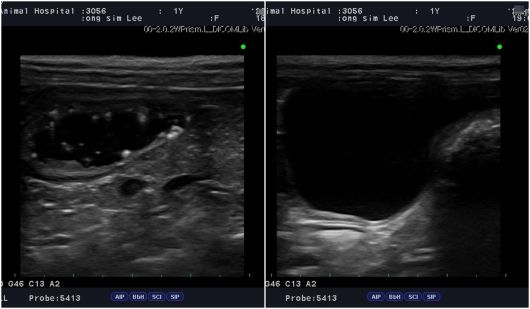

윤 원장이 기억에 남는 건강검진 사례 중 하나는 1살의 어린 반려견이다. 초음파 검사에서 방광 내 심한 슬러지(찌꺼기)가 발견됐다. 이후 요검사 결과 스트루바이트 결정이 확인됐다. 조기에 식이 관리와 치료를 진행한 결과 한 달 만에 슬러지는 말끔히 사라졌다. 그대로 방치됐다면 결석으로 진행돼 외과 수술까지 이어질 수 있었던 상황이었다.

1살 반려견이 건강검진을 통해 방광 슬러지가 확인됐지만 조기 발견 덕에 한 달 만에 회복해 결석을 예방할 수 있었다. 건강검진 당시 초음파 이미지(왼쪽)와 한 달 치료 후 슬러지가 사라진 모습(메인동물병원 제공) ⓒ 뉴스1 |